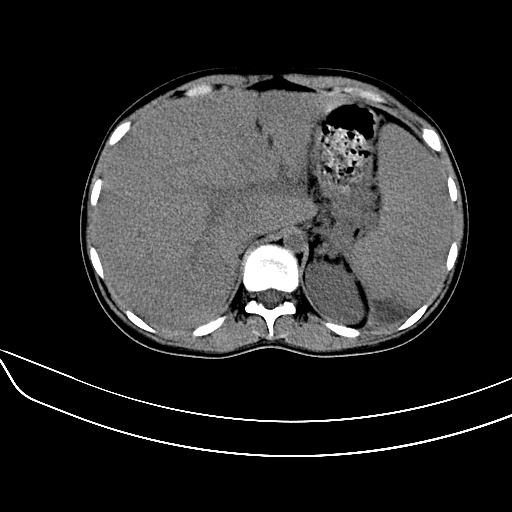

标题: CT7307:糖尿病引起的肝、脾损害?

女,22岁,临床以糖尿病等病史入院,两年前有妊娠合并胰腺炎史,现有多饮、多尿、咳嗽、咳痰、左腰痛、发热等。因多种原因没做增强。

糖尿病并发肝结核,左腹膜后冷脓肿

2、脾包膜下血肿、左侧腹膜后血肿(可能为特发性)。

真可惜,这么年轻就重病缠身,患者肝内,脾,肾,左下肺,左腰大肌均见病变,结合病史考虑感染可能性大。

左肾周感染,腰大肌脓肿,肝脾脓肿?不能增强,就来个mri。